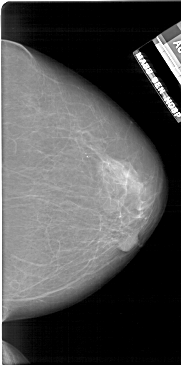

A_1805_1.LEFT_CC

LEFT_CC LINES 6601 PIXELS_PER_LINE 3331 BITS_PER_PIXEL 12 RESOLUTION 43.5 OVERLAY

FILE: A_1805_1.LEFT_CC.OVERLAY

TOTAL_ABNORMALITIES 1

ABNORMALITY 1

LESION_TYPE MASS SHAPE IRREGULAR MARGINS ILL_DEFINED

ASSESSMENT 4

SUBTLETY 1

PATHOLOGY BENIGN

TOTAL_OUTLINES 1

BOUNDARY